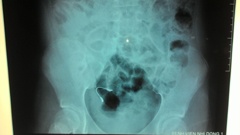

Ngu day, phat hien nieng rang lot vao bung hinh anh

Ngủ dậy, phát hiện niềng răng lọt vào bụng

Ngủ dậy, người nhà phát hiện dụng cụ niềng răng chỉnh hình trong miệng bệnh nhi biến mất. Đến bệnh viện, các bác sĩ phát hiện dị vật là cọng kẽm nằm trong đường tiêu hóa.